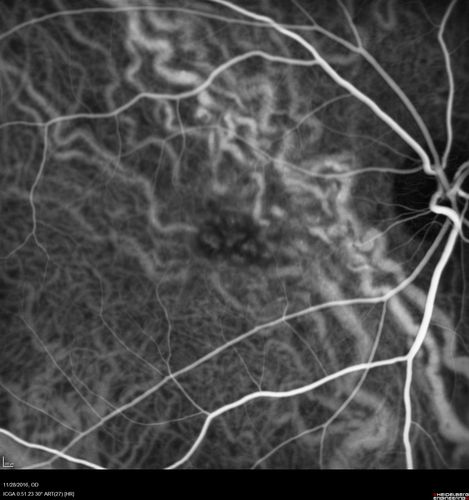

Confluent Soft Drusen with Subetinal Fluid - Right Eye

Asymptomatic 85 year old man.  OCT shows pocket of subfoveal fluid in the center of the macula.  This could be mechanical from the drusen preventing the retina from settling down.  Testing did not reveal a CNVM and subsequent OCT 6 weeks later showed no change in structure.